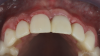

(2.) Preoperative retracted maxillary view of an implant-supported restoration at the site of tooth No. 9 demonstrating a peri-implant soft-tissue dehiscence extending approximately 3-mm apical to the gingival margin of tooth No. 8. Note the thin and erythematous marginal tissue evident at the zenith.

Figure 2

The patient in this case had undergone implant therapy at the site of tooth No. 9 and was restored with a cement-retained restoration more than 5 years prior. At presentation, the site demonstrated a peri-implant soft-tissue dehiscence that extended approximately 3-mm apical to the gingival margin of tooth No. 8. Thin and erythematous marginal tissue was evident at the zenith (Figure 2). The crown was removed, and a partial thickness flap was reflected using a papilla-sparing incision design. This revealed that the implant was positioned too far facially and that its body was visible through a very thin layer of bone (Figure 3 and Figure 4). The first objective of treatment was to minimize the facial extent of the emerging abutment and crown. To accomplish this, the facially positioned abutment and implant crown margin were both recontoured. The second treatment objective was to provide additional supracrestal soft tissue that would more adequately maintain the peri-implant margin. The tuberosity was selected as a donor site due to its dense, high-quality connective tissue, low propensity for shrinkage, and association with minimal patient discomfort. Once the graft was secured (Figure 5 through Figure 7), the flap was coronally positioned (Figure 8). After a healing period of 2 weeks, the margin of tooth No. 9 exhibited an ideal position in relation to its contralateral counterpart and demonstrated increased soft tissue thickness (Figure 9). Three months postoperatively, further healing had improved the esthetics and the position of the margin had been maintained (Figure 10).